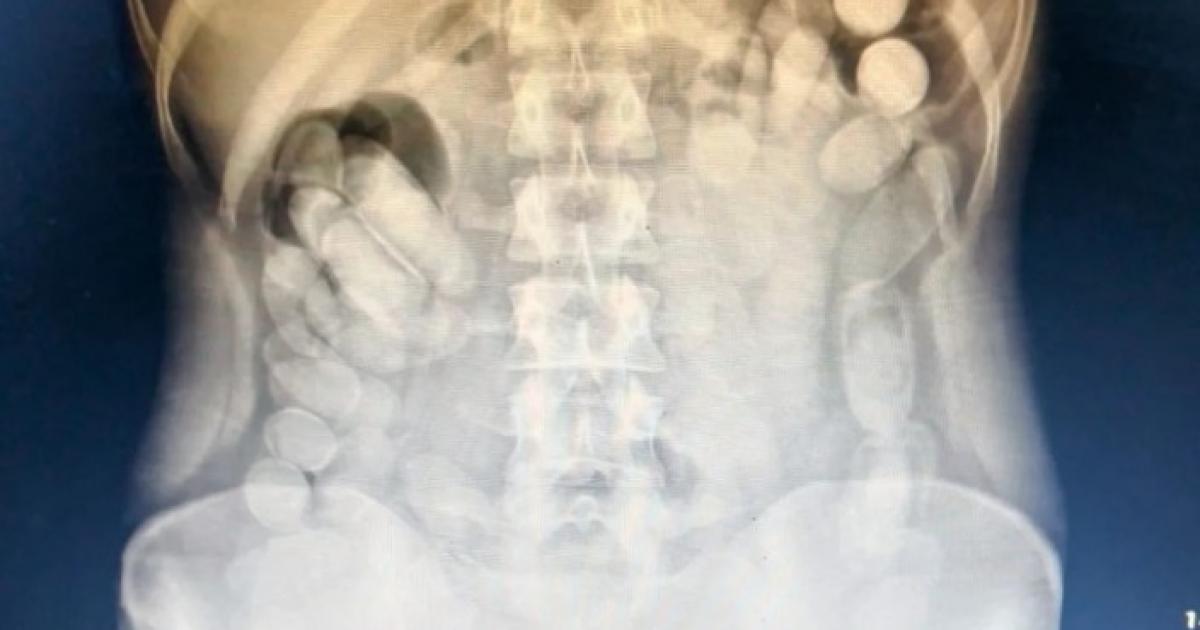

Una vez en el Nosocomio local, se le realizó una radiografía a la mujer mediante la cual se pudo observar la presencia de las dosis en su abdomen. Más tarde, la involucrada evacuó 106 cápsulas.